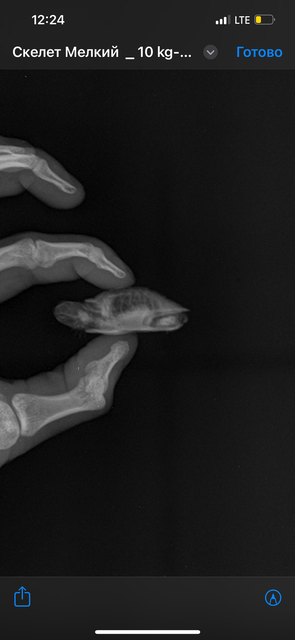

Здравствуйте. Ренген сделали.

IMG_7607.png

IMG_7606.png

IMG_7605.png

@lelka101 камней не видно, уже радует

я отправлю снимки нашему врачу, напишу как она ответит.

@lelka101 врач посмотрела снимки и сказала, что есть помутнения в лёгких, нужен антибиотик. Закажите Марбобел 2%, воду для инъекций и 10 инсулиновых шприцев с шагом 0.01мл. Посмотрите, чтобы между числовыми делениями было 10 делений, а не 5. Черепашка маленькая - будет удобнее набирать, т.к. дозировка будет буквально капля.